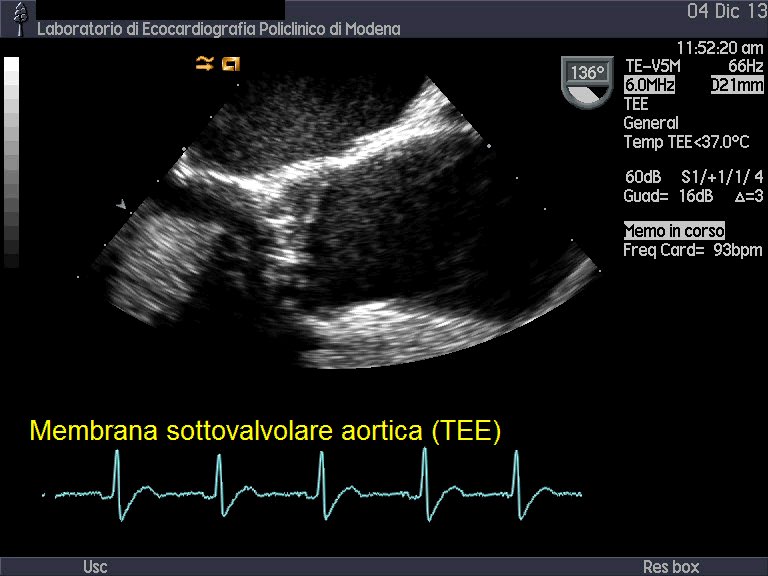

Stenosi sottovalvolare aortica

Autore:

Andrea Barbieri